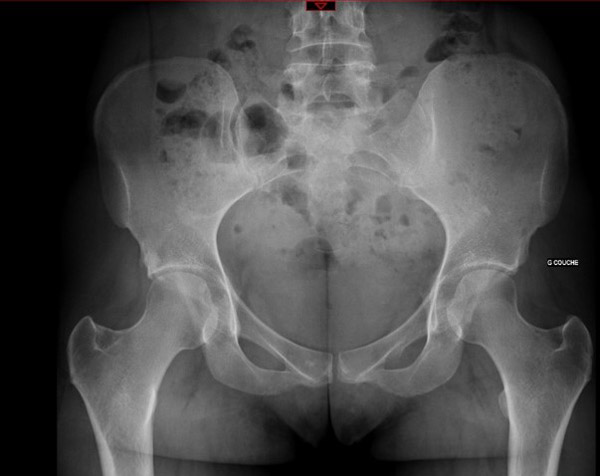

Standard - X-rays

Standard – x-rays

• ✔️ Femoro acetabular impingement Pincer type By TRUE acetabular retroversion (acetabular posterior dysplasia)

3 signs: cross-over sign, ischial spine sign, posterior wall sign

Retroversion index > 30%

Femoro acetabular impingement Pincer type By TRUE acetabular retroversion